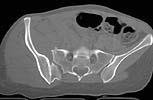

A woman in her 30's in a high speed MVC with this closed pelvic fracture. She's hemodynamically stable, no other injuries - belly, chest, and head are all fine. She also has a comminuted supracondylar femur fracture on the R side.

Preop CT

the enclosed ct image demonstrates her second, not upper sacral segment.

her plain pelvic radiographs indicate upper sacral dysmorphism, which has a significant impact on safe iliosacral screw insertion, regardless of imaging modality chosen to assist insertion.

the ct image reveals no significant posterior pelvic degloving injury, for that single axial image.